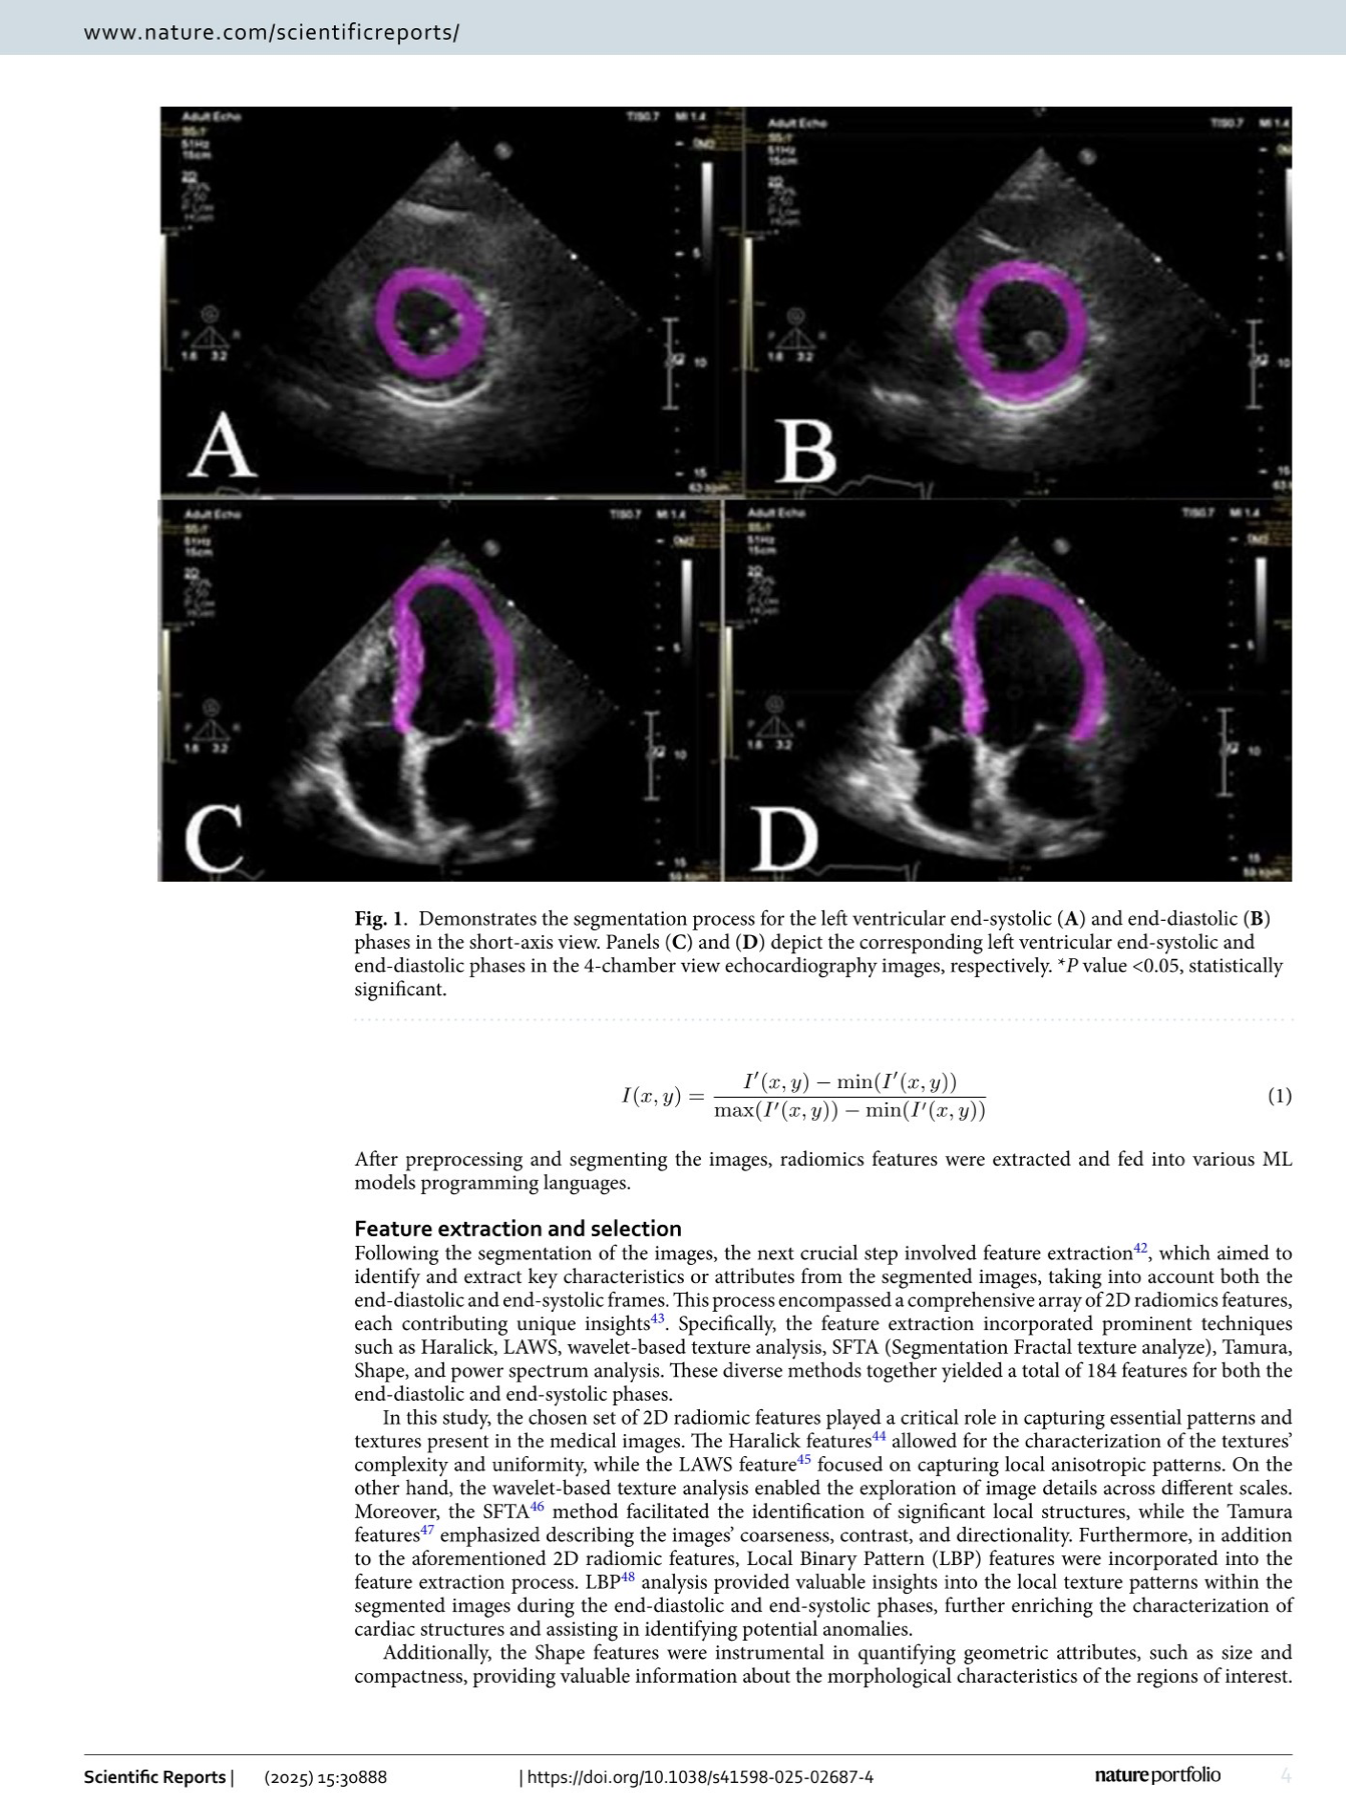

” We’re thrilled that our recent ‘Nature’ publication has received such great feedback.”